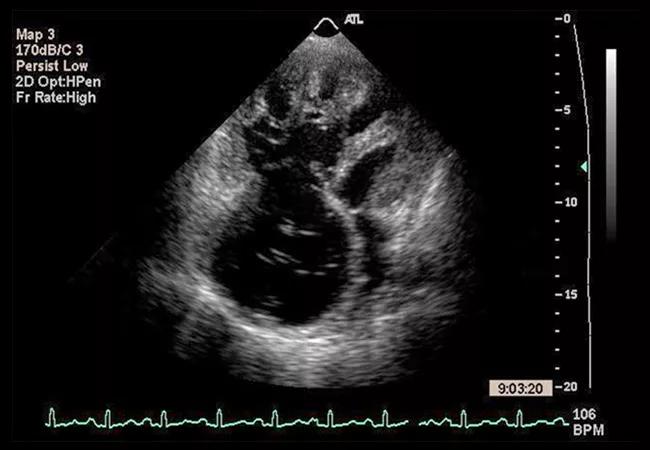

A: A main trigger for the statement was the resurgent interest we’re seeing in RHF because of new treatment strategies. Decades ago, when imaging technologies first enabled insight into the right (and left) heart anatomy, people were excited about right heart dysfunction. Then, for many years it became the forgotten ventricle, partly because there are so many nuances that make it hard to understand, and partly because the left ventricle gets center stage for being the primary pump. Now we have new treatment strategies for pulmonary hypertension and new technologies to mechanically support patients with RHF.

A: One is that we need to step up the rigor with which we explore what the right heart is doing. For example, experts in advanced heart failure tend to be aggressive about measuring right heart hemodynamics to assess options, starting with imaging and then confirming with catheterization. But some cardiologists delay that confirmation a little later than they should or forgo it altogether, since it’s invasive. They ask, “What’s it going to change?” But a cath, when performed early on, is key to confirming imaging and distinguishing between intrinsic right ventricular pathology versus pulmonary vascular obstructive disease versus LHF. These diagnoses can drive different therapies.

A: There’s a tendency to underestimate the interdependence of the right ventricle with other heart structures and with other organs and systems — the upstream triggers and downstream impact of right heart dysfunction. Diagnosing right heart dysfunction and treating it early can prevent the cascade of damage that chronic congestion and malperfusion can wreak on multiple organs. This understanding can be elusive, and the urgency can be underestimated in general cardiology practice.

A: We needed a comprehensive paper that expresses the complexity of RHF and the comorbidities that frequently overlap it. Much has been written about LHF and, separately, specific topics such as right ventricular dysfunction, echo and pulmonary hypertension, for example. But these topics have to be considered together if we are to provide proper care.